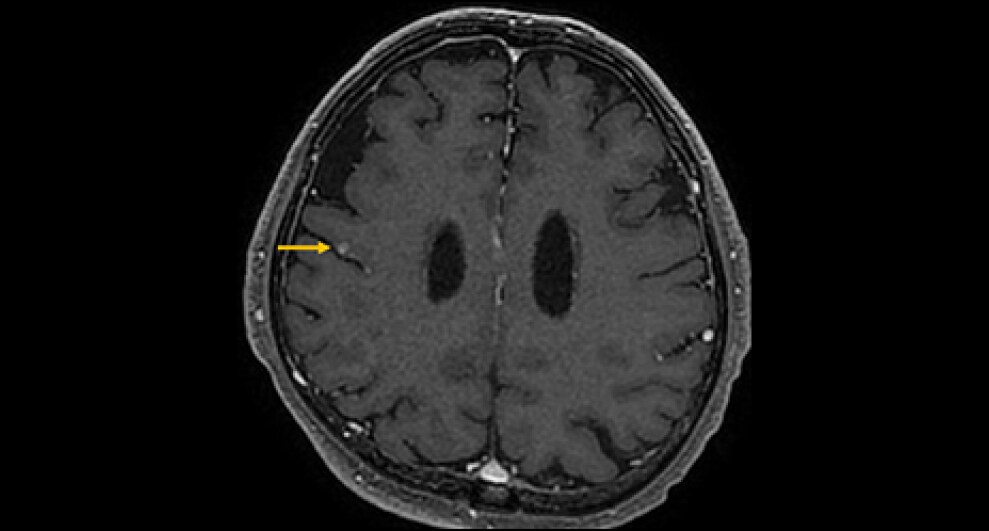

症例は70歳代男性。物が二重に見える、ふらつくとの訴えで来院。非造影MRIにて脳幹部や小脳に4個の多発脳腫瘍が認められ、症状と合致した。全身精査にて進行胃癌が発見され、その脳転移と診断された。放射線治療の適応判定のため造影MRIを施行し、新たに大脳に3個の微小転移が同定された。病変のサイズ・分布から微小転移を含む7個の腫瘍に対して定位放射線治療が可能と判断され、速やかに治療導入に至った。

本症例では先行する非造影MRIにて右中脳や左小脳の多発腫瘤が指摘され、周囲に浮腫を伴うことから転移が疑われていたが、病変数や大きさ・範囲ははっきりしなかった。造影MRIを実施することにより、右中脳に1個、左小脳に3個の2㎝大の輪郭の明瞭な腫瘍が確認されたほか、1㎝未満の3個の微小病変を新たに検出できた。非造影MRIを見直したところ7㎜の結節はFLAIRでも淡い高信号を示していたが質的診断は困難であった。3㎜の病変は非造影MRIでは存在診断不能であった。微小病変のうち2個は高位前頭葉の機能的に重要な部位に位置しており、治療適応と考えられた。造影MRIにより腫瘍の正確な個数とサイズ、分布の正確な情報を確認した後、定位放射線治療が可能と判断され、3D-FSPGR画像を治療計画に利用して迅速に治療が開始された。